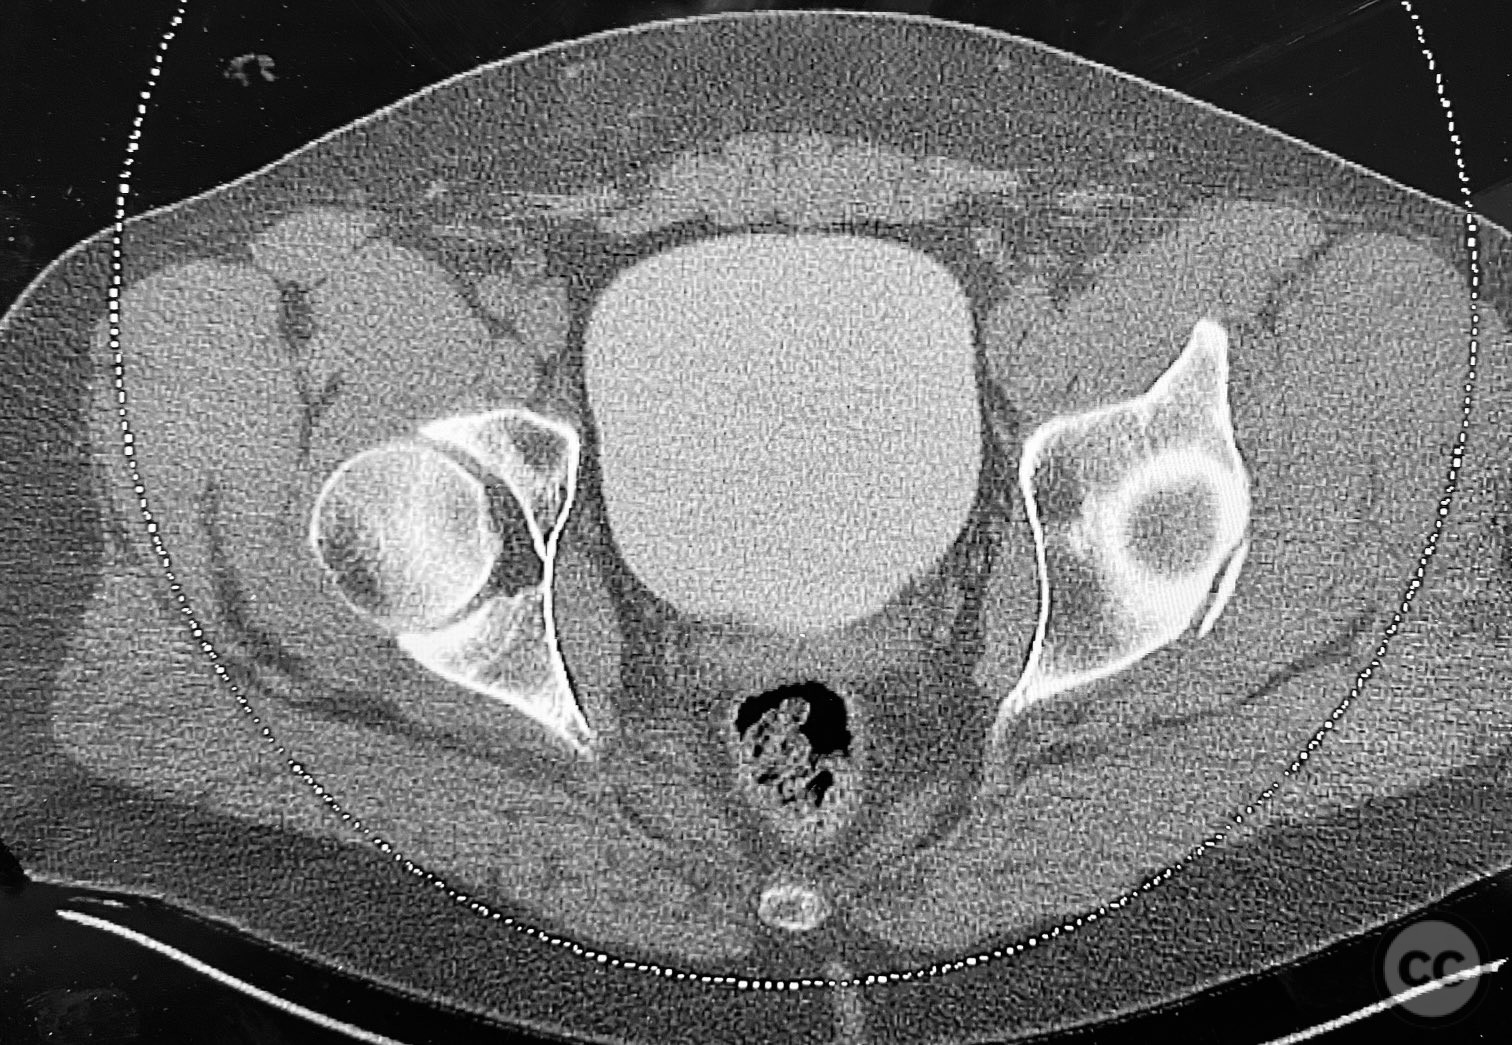

Clinical and radiological findings:  A patient involved in a motor vehicle collision presented with left hip pain exacerbated by any attempted movement. Initial axial and surface-rendered computed tomography (CT) imaging demonstrated an essentially nondisplaced posterior wall (PW) acetabular fracture (AO/OTA 62-A1.1). However, the anteroposterior (AP) scan image and coronal reconstructions revealed significant hip joint asymmetry. Examination under anesthesia with fluoroscopic guidance confirmed persistent joint incongruity, with the femoral head subluxating posteriorly at 50–60 degrees of flexion. A pure chondral fragment was identified as being interposed between the femoral head and the intact region of the posterior wall, accounting for the clinical and radiological asymmetry.